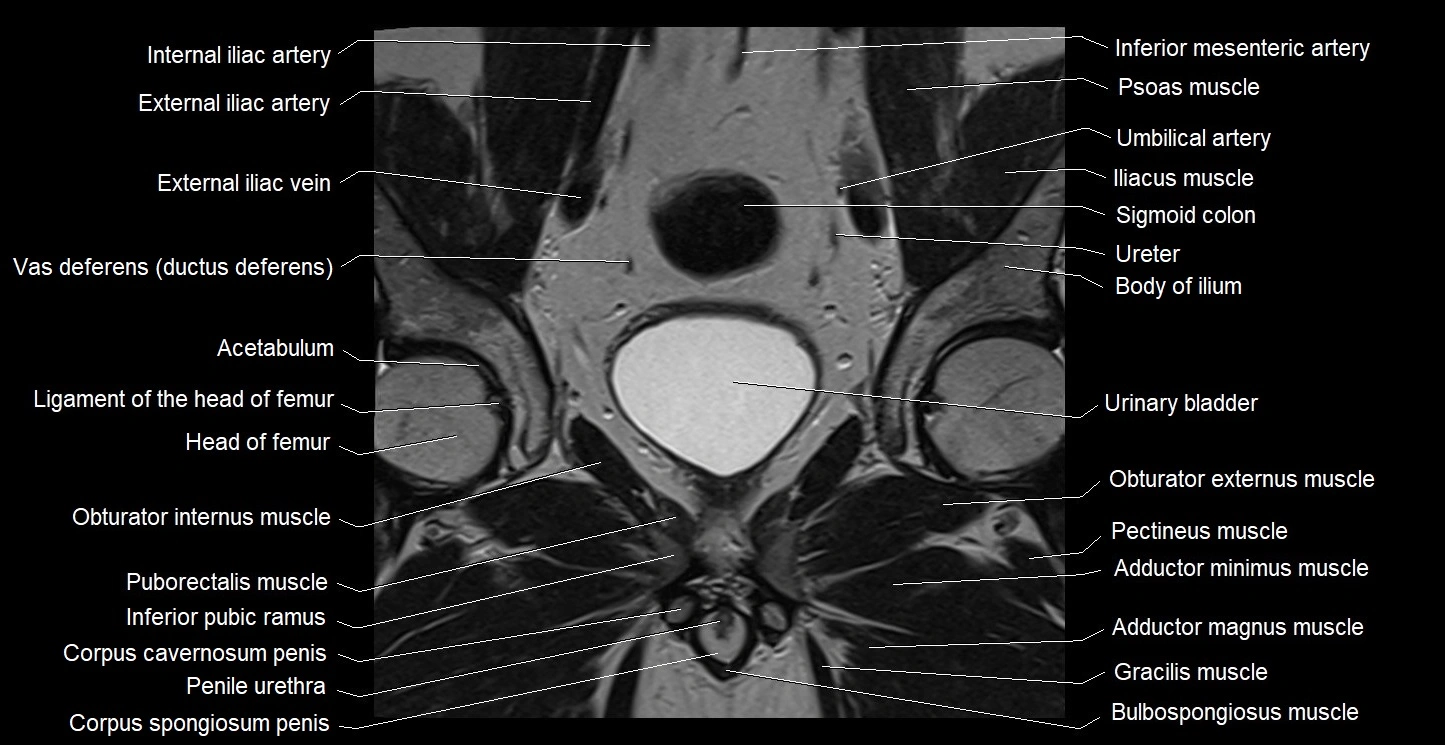

- Acetabulum

- Body of ilium

- Bulbospongiosus muscle (Male)

- Corpus spongiosum

- External iliac artery

- External iliac vein

- Femoral nerve

- Gracilis muscle

- Head of femur

- Iliopsoas muscle

- Inferior mesenteric artery (IMA)

- Inferior pubic ramus

- Internal iliac artery

- Ligamentum teres (ligament of the head of femur)

- Median umbilical ligament

- Obturator externus muscle

- Obturator internus muscle

- Pectineus muscle

- Penile urethra

- Psoas major muscle

- Puborectalis muscle

- Sigmoid colon

- Superior pubic ramus

- Umbilical artery

- Urinary bladder

- Vas deferens